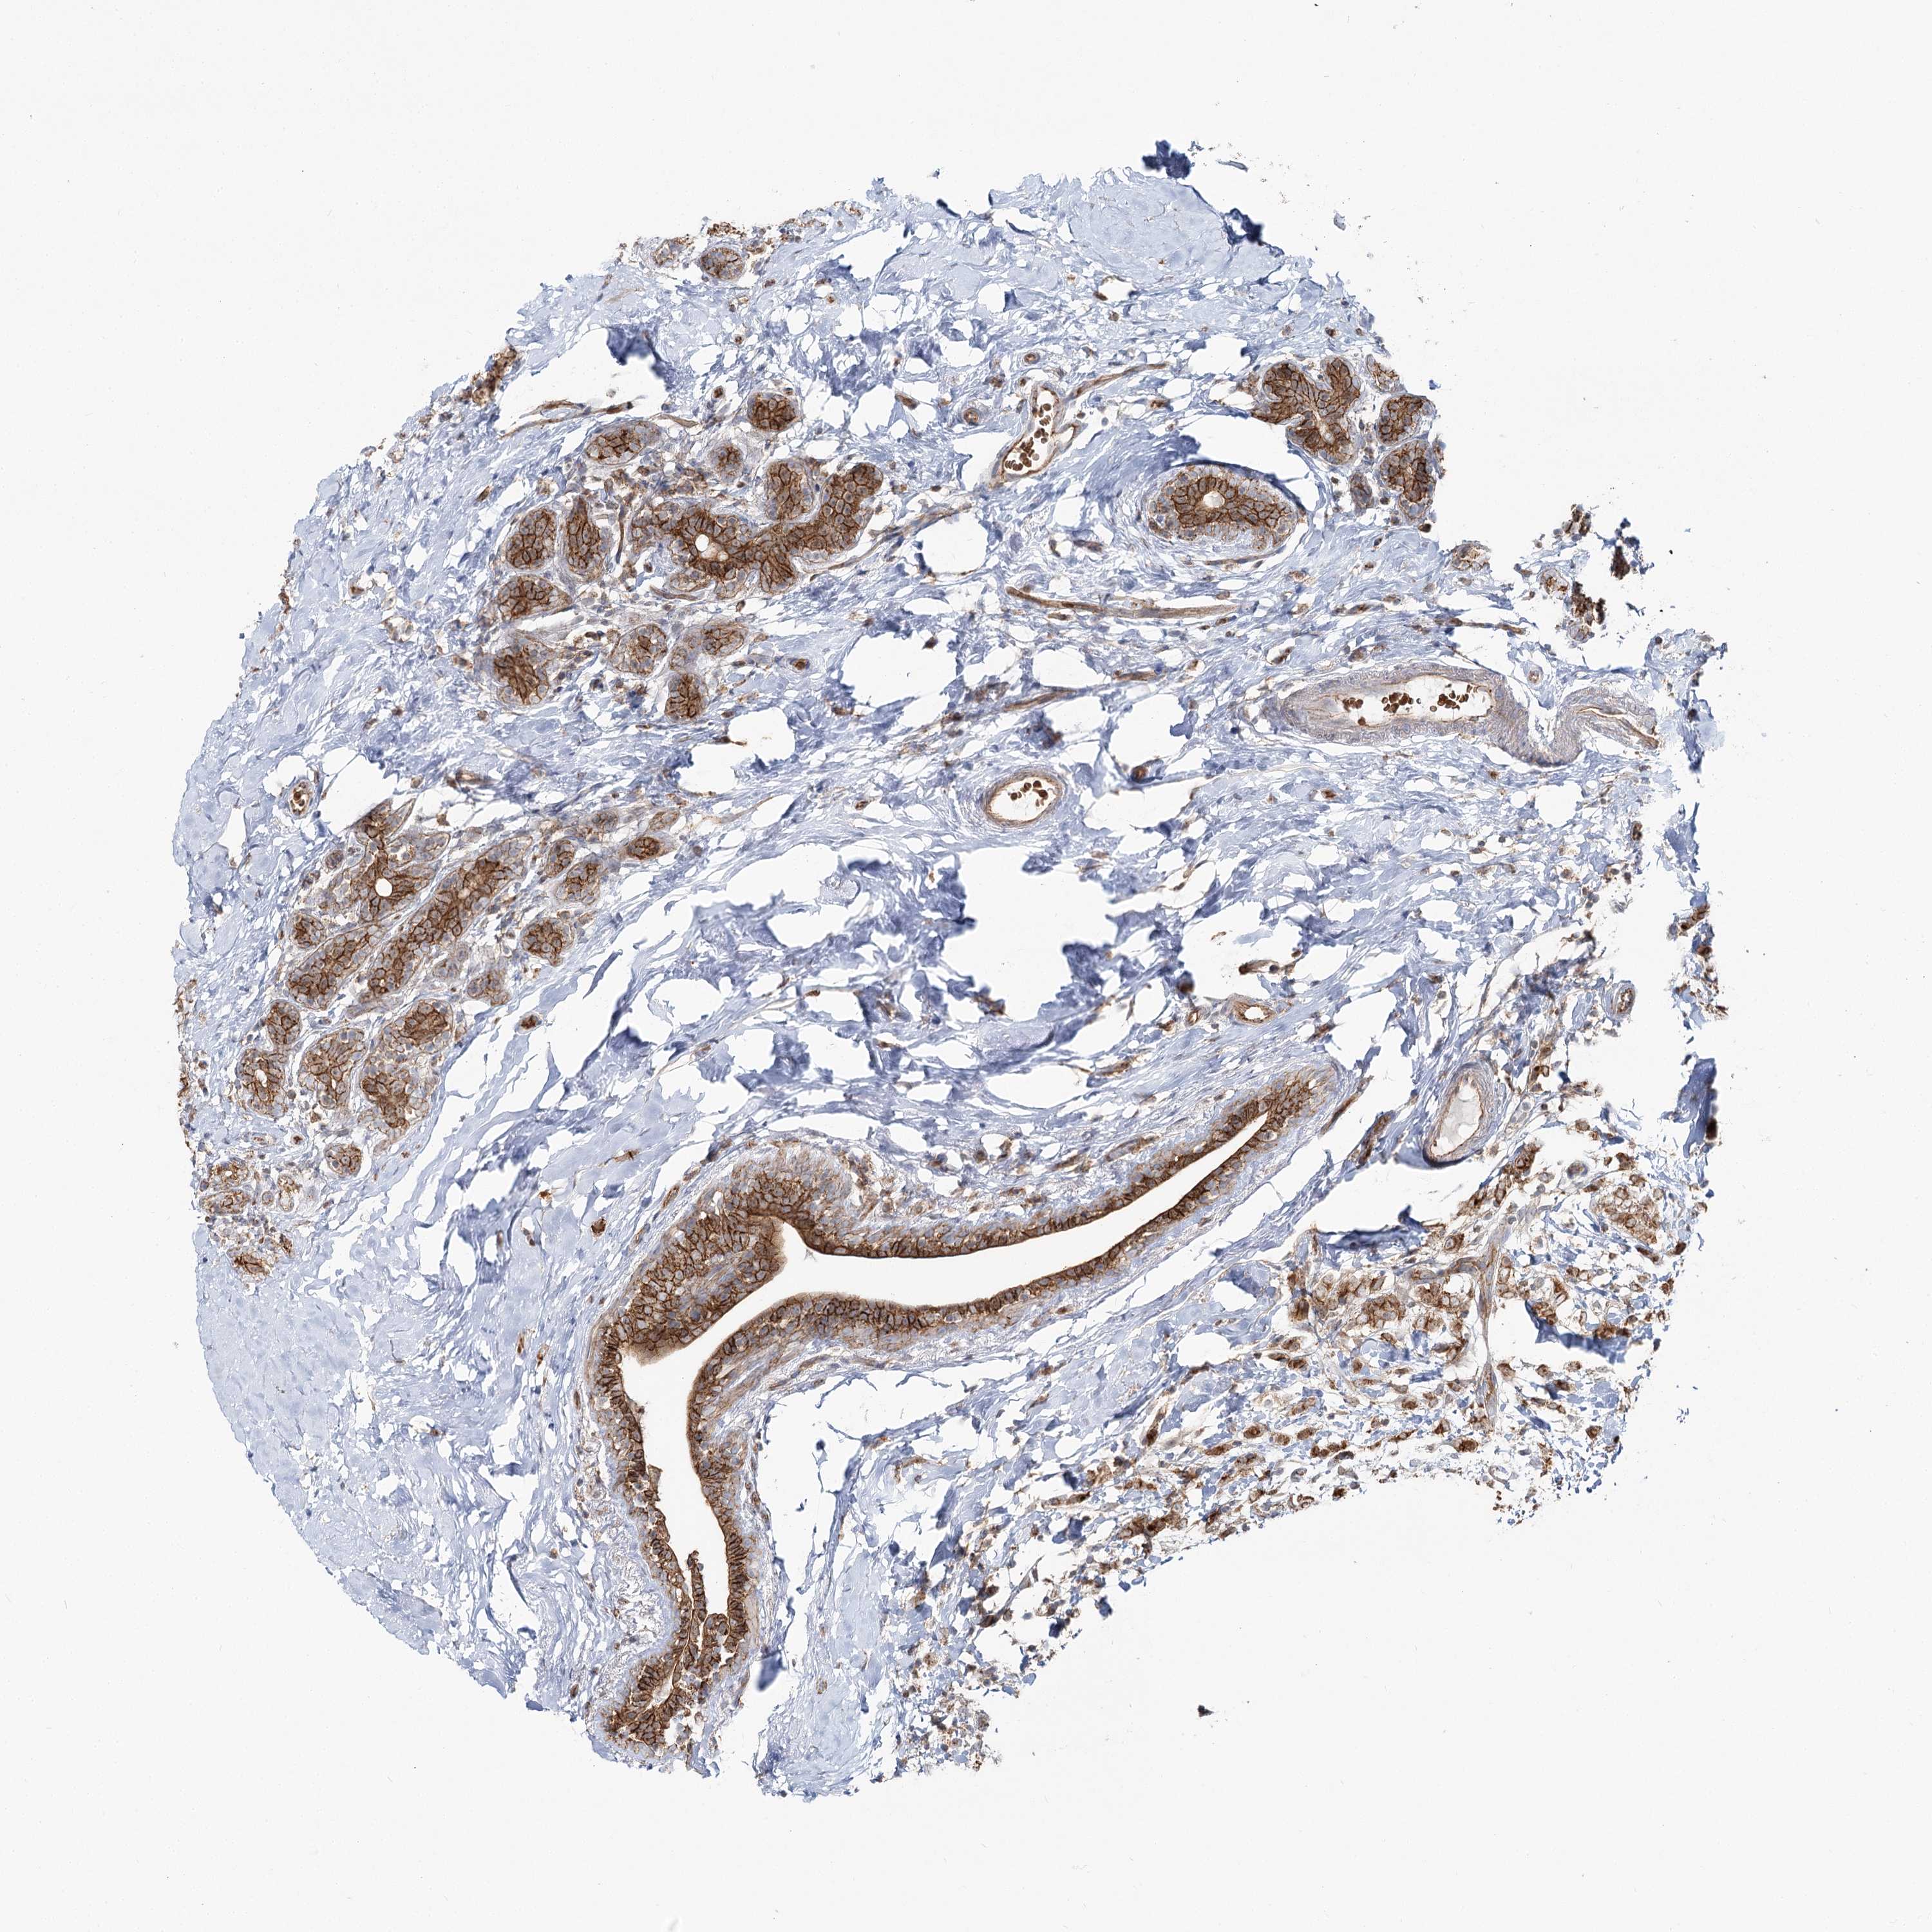

CANCER BREAST CANCER Show tissue menu

BRCA TCGA BRCA VALIDATION PROTEIN EXPRESSION